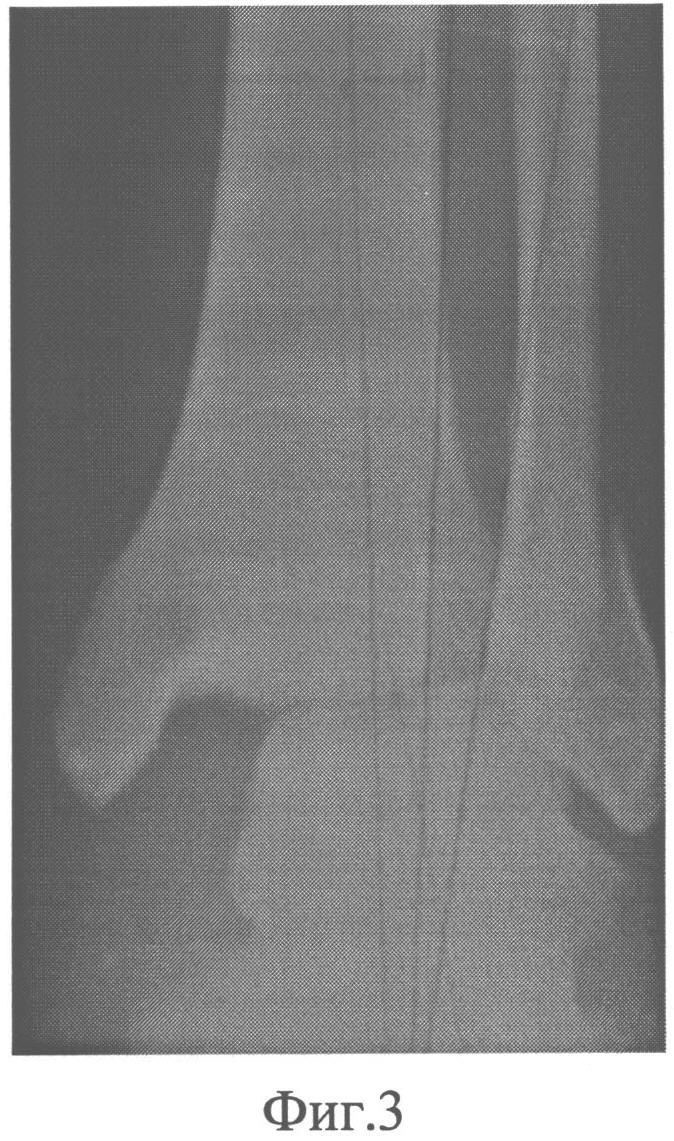

на фиг.3 - первичная рентгенограмма голени больного при поступлении;

Пациент Т., 1967 г.р., ист./б. №902, находился на лечении в отделении травматологии с 28.02. по 09.03.2009 г. с диагнозом: закрытый перелом наружной лодыжки, повреждение дельтовидной связки, дистального межберцового синдесмоза справа, подвывих стопы кнаружи. На рентгенограмме (фиг.3) имеет место перелом наружной лодыжки со смещением, повреждение дистального межберцового синдесмоза, подвывих стопы кнаружи. Операция: закрытый ЧКОС перелома дистального суставного отдела костей голени аппаратом внешней фиксации 04.03.2009 г. В нижнюю треть и дистальный метафиз большеберцовой кости и пяточную кость введены костные стержни Шанца, закреплены на кронштейнах кольцевой и дуговой опор аппарата внешней фиксации, в дистальный отломок наружной лодыжки введен аналогичный стержень, закреплен на кронштейне, установленном на кольцевой опоре аппарата (фиг.4). Аппарат демонтирован, снят 28.04.2009 г. Курс восстановительного лечения в стационаре. Контрольный осмотр 04.10.2010 г., 16.10.2012 г. Пациент жалоб не предъявляет. Трудоспособность восстановлена. Нагрузка на стопу полная. Движения в голеностопном суставе в полном объеме. Исход лечения оценен как отличный (фиг.5).